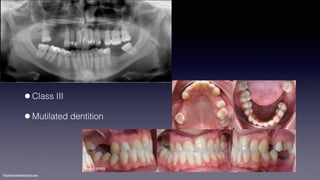

•Class III

•Mutilated dentition